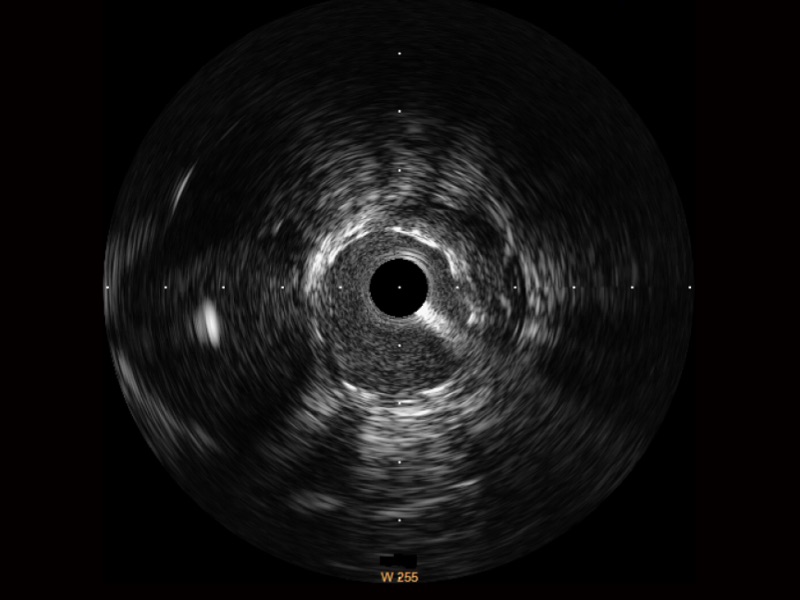

1xBET宽频IVUS图像

对比传统IVUS导管成像,1xBET宽频IVUS图像的近场支架梁显影更细腻,远场中膜外血管仍清晰可辨,兼顾远中近,兼顾分辨力与穿透深度